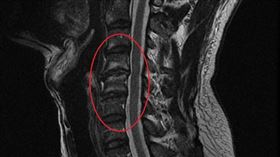

52歲男突易怒暴躁 竟「痺證」上身

現代人工作壓力大,又常當低頭族,時間久了時常感到肩頸...